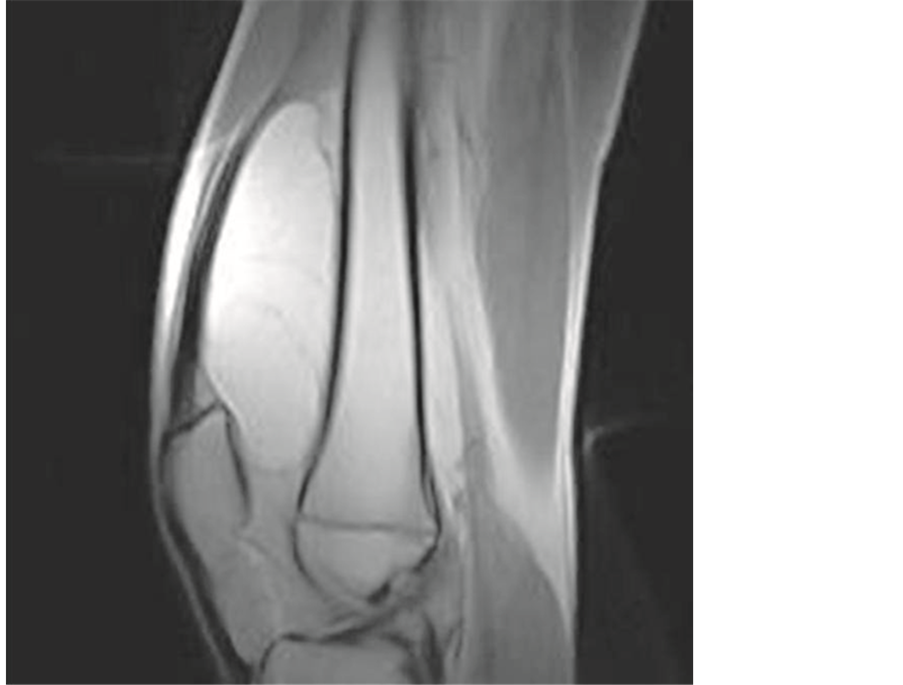

To characterize the lesion and define the compression of adjacent neurovascular bundle, magnetic resonance imaging (MRI) was performed [7] . It revealed a well-defined, multilobulated, and juxtacortical bony excrescence measuring 8 × 4.7 cm in size at the lower end of the left femur. It had no contiguity with marrow space of the distal femur differentiating it from an osteochondroma. There was mild enhancement of interface between the bony protuberance and the lipid component of the lesion suggesting the fibrous tissue rim. There were no findings of neurovascular bundle compression. The diagnosis of parosteal lipoma with bony excrescence was made [8] [9] .

Figure 3. MRI Images showing the tumoral mass and the dilineation.